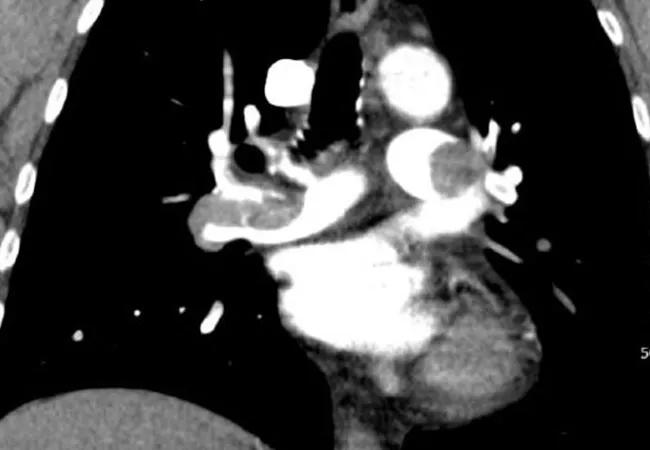

The availability of a multidisciplinary pulmonary embolism response team (PERT) was associated with improved patient outcomes, including 30-day inpatient mortality, in the first published study of outcomes among all patients with pulmonary embolism (PE) before and after the launch of a PERT in a tertiary care hospital. Moreover, patients with more severe PE appeared to derive the greatest benefit from PERT availability.

Cleveland Clinic’s PERT was launched in July 2014. The current study was conducted to compare outcomes of all patients with PE at Cleveland Clinic’s main campus before and after launch of the PERT. Consecutive adults admitted with CT-diagnosed acute PE in 18-month periods before and after PERT implementation were retrospectively identified and analyzed.